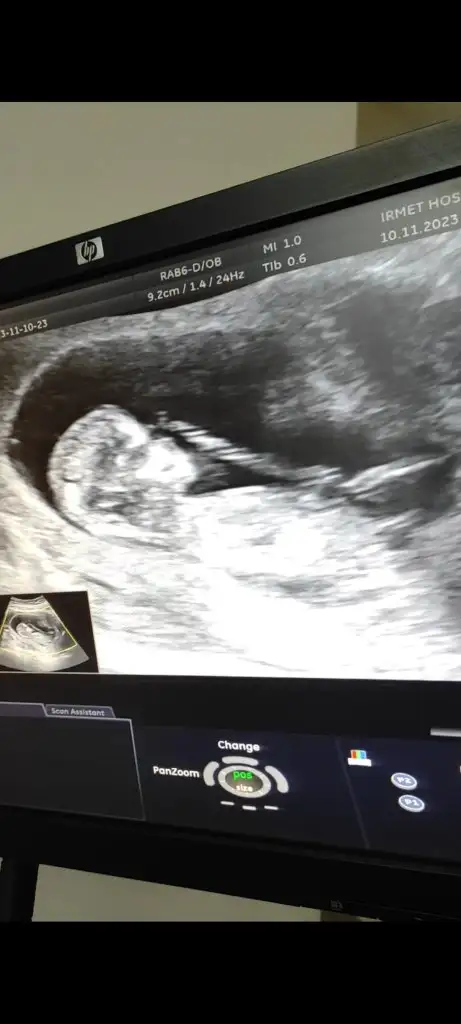

Cinsiyet tahmini olan var mı 12. Hafta🥰

Eklentiler

• Screenshot_2023-11-10-16-48-35-263_com.miui.gallery.webp

Screenshot_2023-11-10-16-48-35-263_com.miui.gallery.webp

19,3 KB · Görüntüleme: 98

• Screenshot_2023-11-10-17-08-58-168_com.miui.gallery.webp

Screenshot_2023-11-10-17-08-58-168_com.miui.gallery.webp

15,3 KB · Görüntüleme: 97

• IMG_20231110_155302_1.webp

IMG_20231110_155302_1.webp

32,8 KB · Görüntüleme: 128